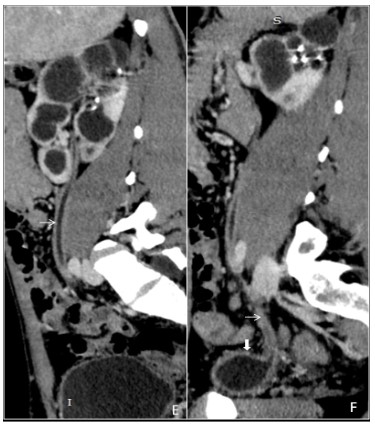

Pancreatic tuberculosis

Isolated tuberculosis of the pancreas is rare, even in countries with a high prevalence of tuberculosis. Pancreatic tuberculosis represents solitary or multiple lesions with multiple necrotic areas. It usually occupies the pancreatic body or head, (Figure 9A,9B) and peripancreatic lymphadenopathy can also be found. The cystic component appears hypoechoic (sometimes hypo-isoechoic) on ultrasound and hypodense on CT scan [9].

Figure 9: (A,B) A 30 years old male patient with constant and chronic vague pain in the epigastric region undergone a contrastenhanced computed tomography of abdomen. The axial and reformatted coronal plane images from the venous phase show a bulky pancreas having intraparenchymal collections (white arrows), peripancreatic fat stranding (thick white arrows) and enlarged lymph nodes (black arrow). It was later diagnosed as pancreatic tuberculosis on fine-needle aspiration from the cystic component. Standard antituberculous therapy involving at least four drugs remains the cornerstone of the treatment. Therefore, the patient has been on ATT for the last three months.